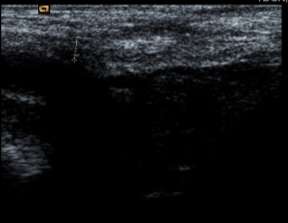

Hình 3.2. Hình ảnh siêu âm mô xơ ở vùng bẹn trái, xuất hiện đường tăng âm với bóng đen cản âm ở phía sau. Bệnh nhân: Phan Văn S. 59 tuổi, Nam.

Bảng 3.27. Phân bố độ dày mô xơ của tấm lưới dưới siêu âm

Số trường hợp | Tỉ lệ (%) | |

Mô xơ dày | 121 | 100 |

Mô xơ mỏng | 0 | 0 |

Tổng | 121 | 100 |

Độ dày mô xơ | 2,51 ± 0,21 mm | 2,1 - 3,5 mm |

Bảng 3.28. Phân bố vị trí tấm lưới dưới siêu âm

Nằm ngay ống bẹn | 121 | 100 |

Di lệch, di chuyển | 0 | 0 |

Mô xơ tạo thành quanh tấm lưới nằm ở vùng bẹn 100%, không có di chuyển và di lệch.